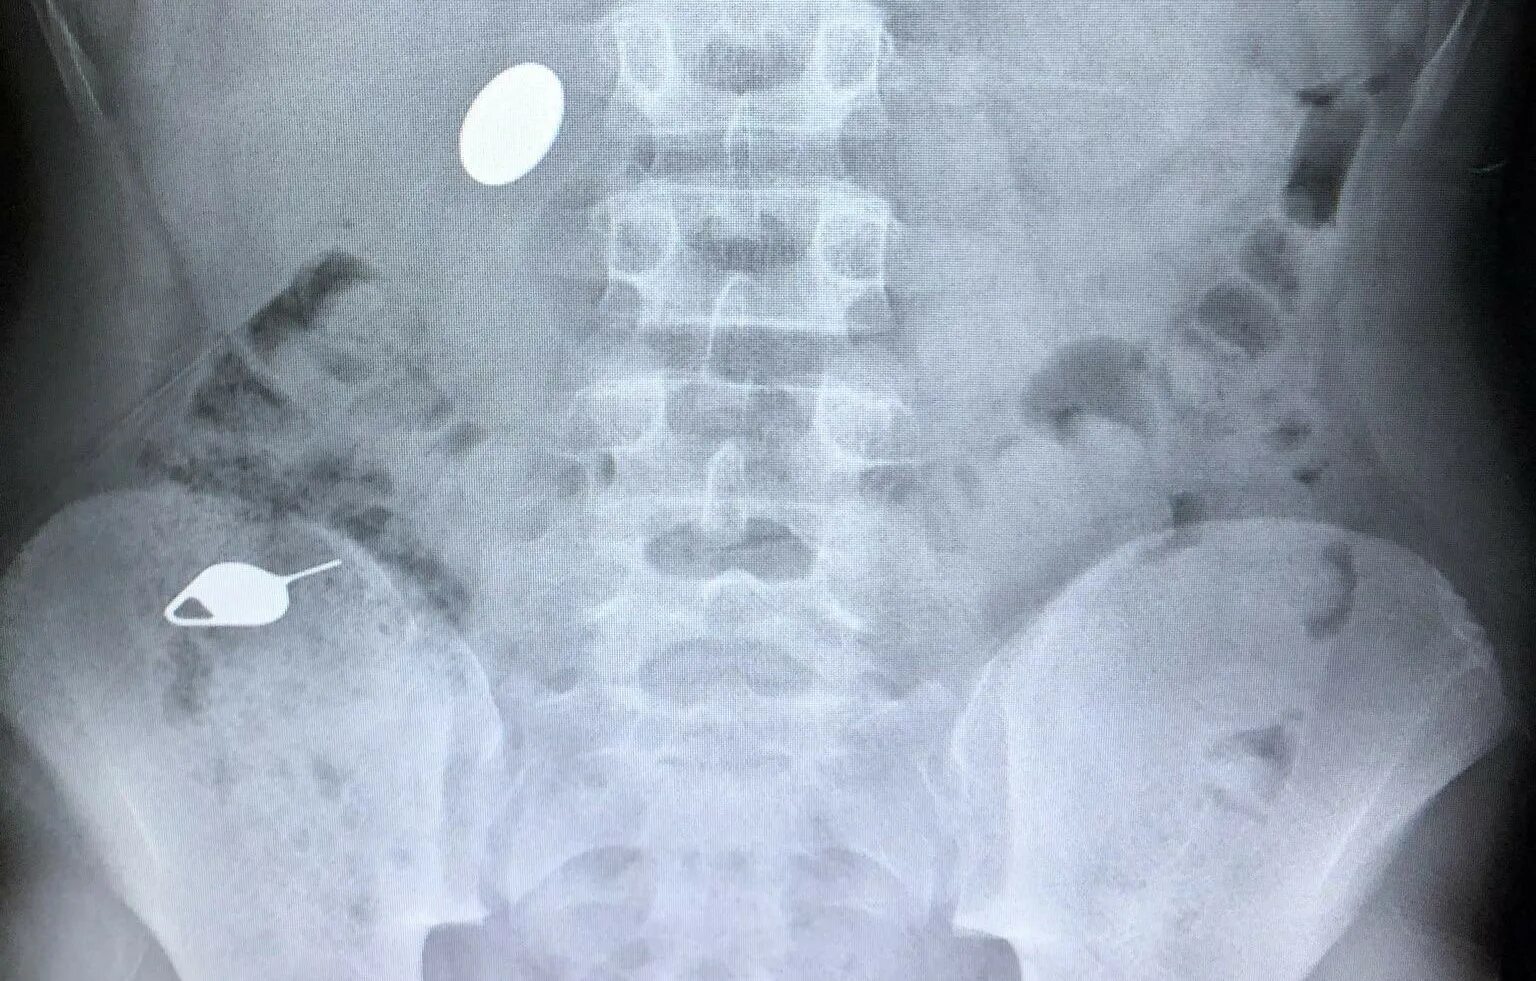

Что делать ребенку год проглотил монету